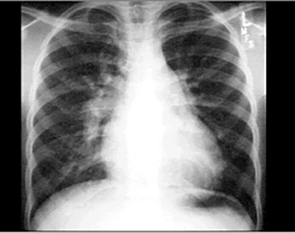

Chest X Rays

PA and Lateral

Click on the Xrays to enlarge them.

Choose the best interpretation of the chest X rays:

Dilated pulmonary trunk

RV enlargement + dilated

pulmonary trunk +

increased pulmonary vascularity

RV enlargement +

LA enlargement

RV enlargement + small pulmonary trunk +

decreased pulmonary vascularity

Normal